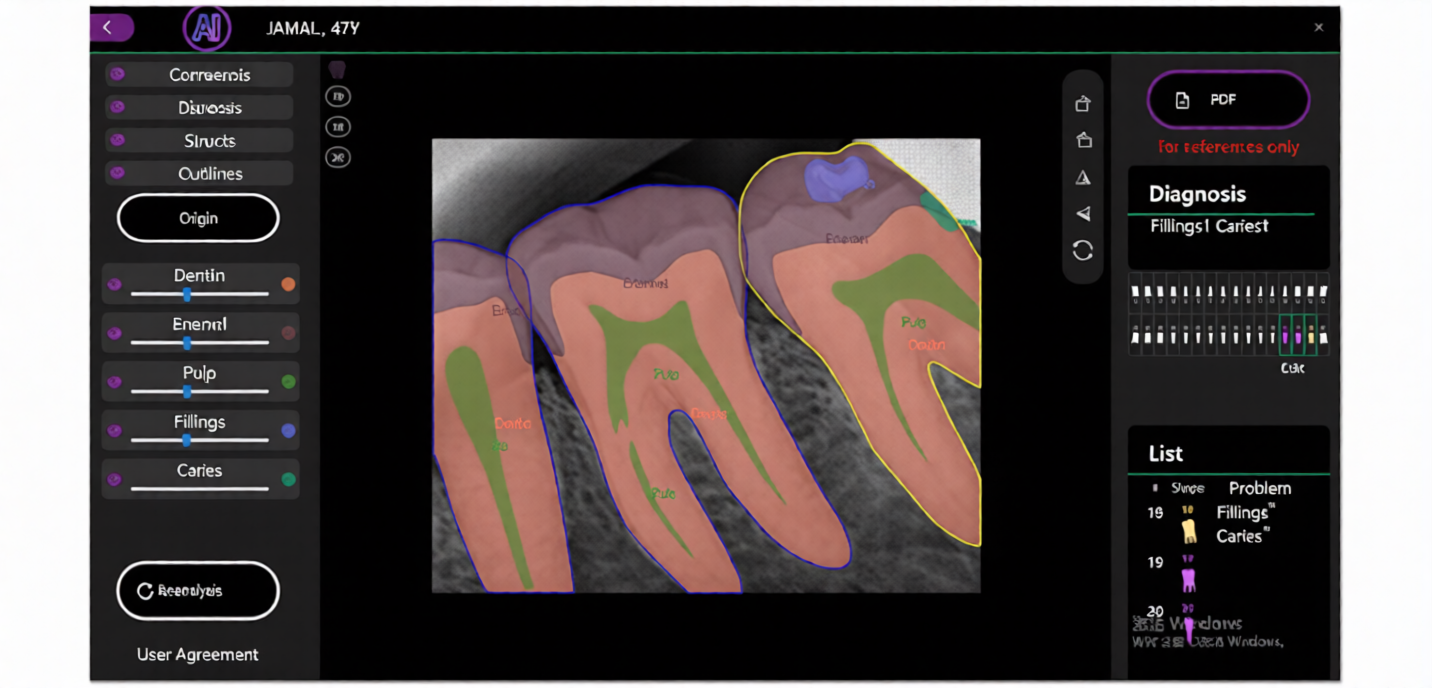

1. AI-Enhanced Imaging Technology

This Professional Dental Digital X-Ray Sensor AI-Enhanced uses advanced imaging technology to produce clear, detailed images. AI-enhanced processing helps improve image sharpness and diagnostic precision.

2. High-Resolution Dental Imaging

The Dental X-Ray sensor provides high-resolution imaging that allows dentists to examine teeth, roots, gums, and jaw structure more effectively.

Quick Diagnosis

AI-enhanced imaging supports dentists in identifying issues faster.

Improved Diagnostic Confidence

Clear and detailed imaging helps dentists make accurate decisions.